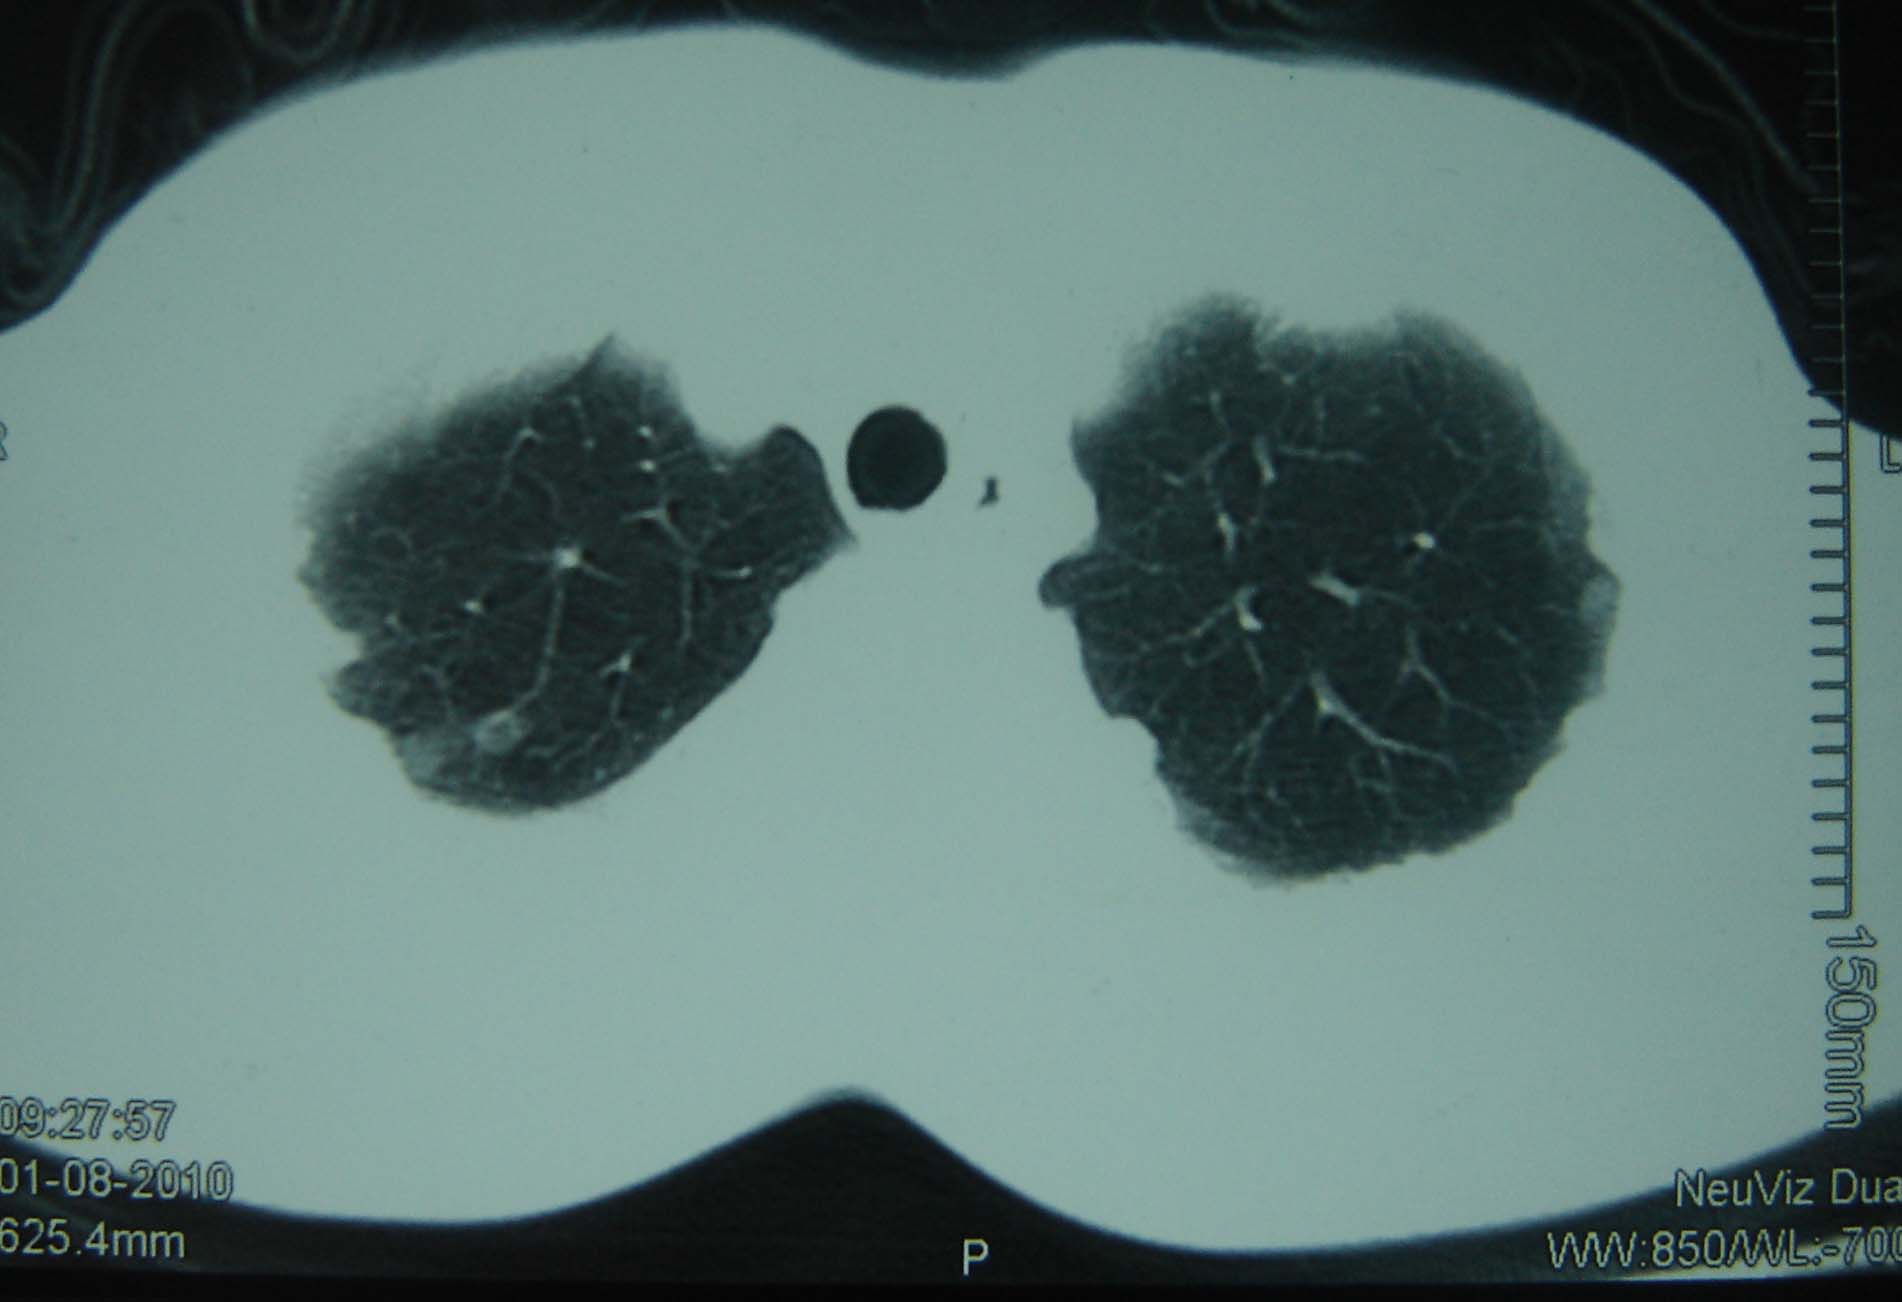

标题: CT25321:两肺多发结节 请会诊 [打印本页]

男 、43岁,咳嗽胸痛,装修工,平时接触粉尘较多,有吸烟史10多年,纤维支气管镜检查未发现异常,胃镜、腹部b超检查亦未发现异常,颈部淋巴结活检未发现肿瘤细胞。